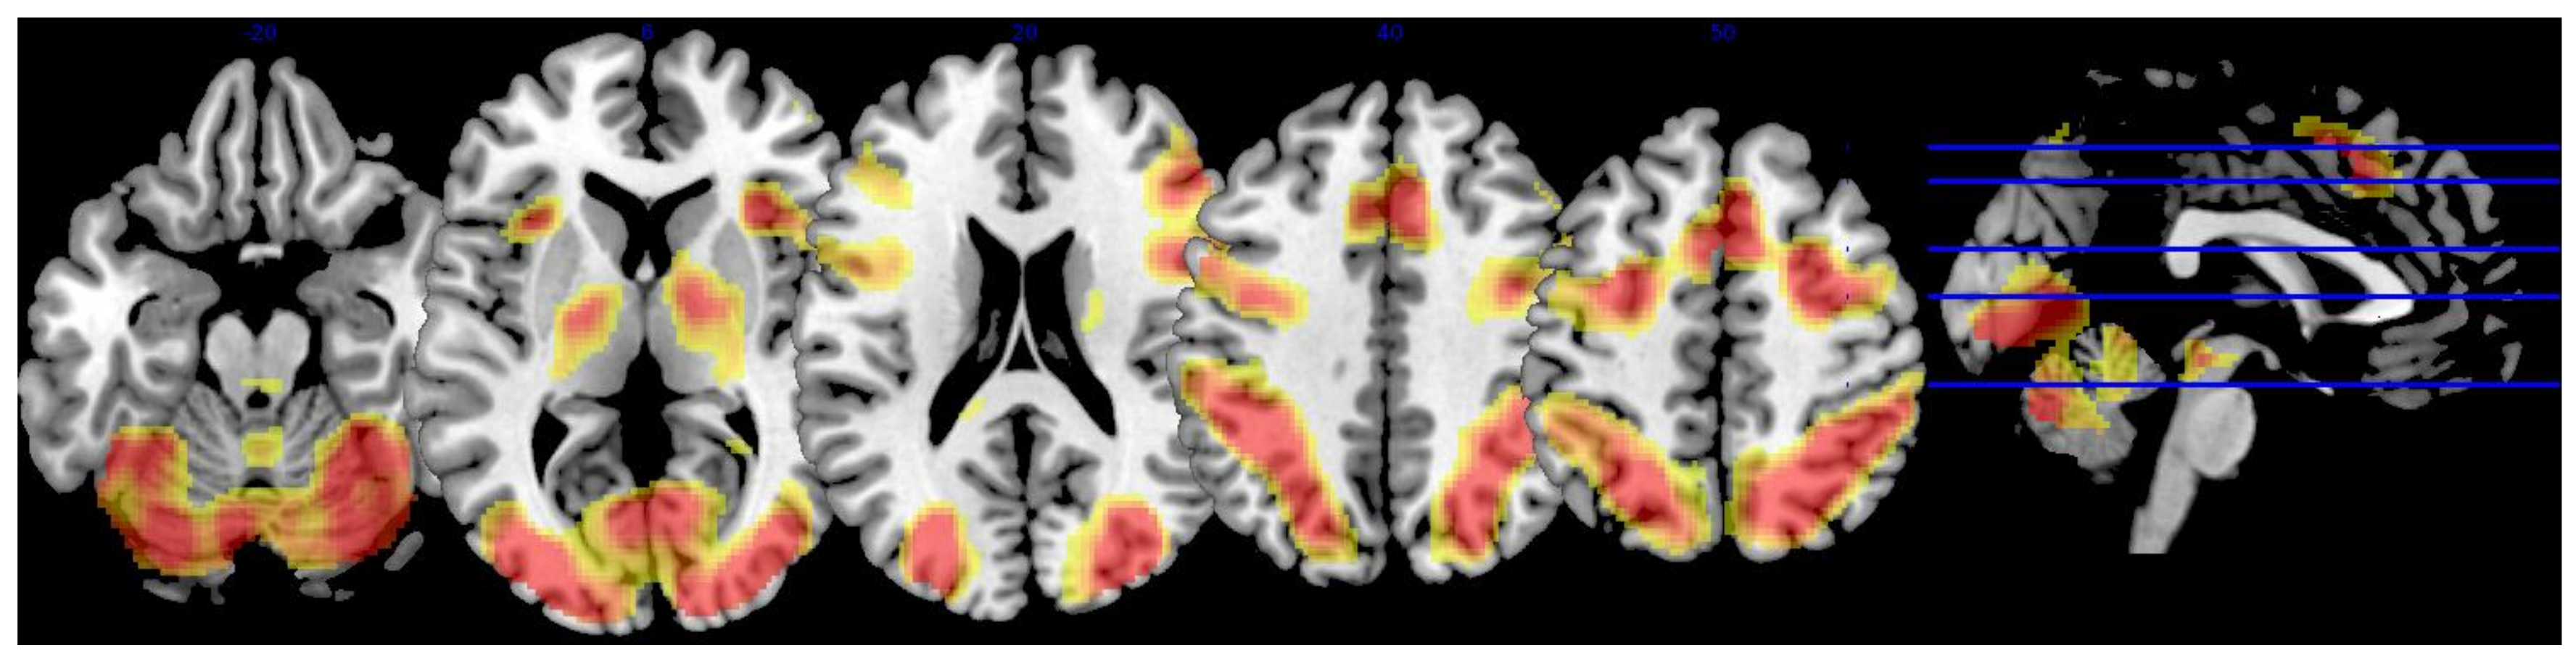

3.2. Whole-Brain Analysis

| Region | x | y | z | Extent | T-Score |

|---|---|---|---|---|---|

| L superior lateral occipital cortex | −32 | −88 | 12 | 35,624 | 23.75 |

| L inferior lateral occipital cortex | −34 | −88 | 2 | * | 21.38 |

| −38 | −86 | 0 | * | 21.21 | |

| −42 | −64 | 12 | * | 20.35 | |

| R superior lateral occipital cortex | 34 | −80 | 22 | * | 21.63 |

| 22 | −64 | 52 | * | 21.58 | |

| 38 | −78 | 12 | * | 20.03 | |

| 26 | −72 | 36 | * | 18.76 | |

| 28 | −74 | 30 | * | 18.40 | |

| R inferior lateral occipital cortex | 34 | −88 | 0 | * | 19.59 |

| 38 | −84 | 4 | * | 19.18 | |

| 40 | −84 | −4 | * | 18.52 | |

| R occipital pole | 18 | −96 | 6 | * | 18.81 |

| R superior parietal lobule | 32 | −52 | 46 | * | 18.38 |

| L cerebellum, vermis VI | −4 | −72 | −26 | * | 18.31 |

| R occipital fusiform gyrus | 38 | −70 | −10 | * | 18.06 |

| R paracingulate gyrus | 6 | 20 | 44 | 13,072 | 18.85 |

| L paracingulate gyrus | −6 | 14 | 46 | * | 14.77 |

| −8 | 24 | 38 | * | 12.37 | |

| R middle frontal gyrus | 28 | 0 | 52 | * | 17.54 |

| 46 | 24 | 24 | * | 14.25 | |

| 50 | 30 | 28 | * | 13.01 | |

| L middle frontal gyrus | −26 | −2 | 52 | * | 13.90 |

| −38 | 28 | 22 | * | 9.60 | |

| R insular cortex | 32 | 20 | −2 | * | 17.48 |

| L insular cortex | −34 | 20 | 0 | * | 15.28 |

| R precentral gyrus | 42 | 6 | 28 | * | 17.15 |

| L precentral gyrus | −32 | −4 | 48 | * | 14.83 |

| −46 | 4 | 30 | * | 13.30 | |

| R frontal pole | 44 | 44 | −14 | * | 13.23 |

| 38 | 58 | 0 | * | 11.16 | |

| 46 | 50 | −8 | * | 10.16 | |

| L cingulate gyrus | −6 | 0 | 26 | 75 | 8.24 |

| L frontal pole | −46 | 48 | −4 | 30 | 8.05 |

| −48 | 44 | −8 | * | 7.63 | |

| −42 | 52 | 6 | * | 7.06 |